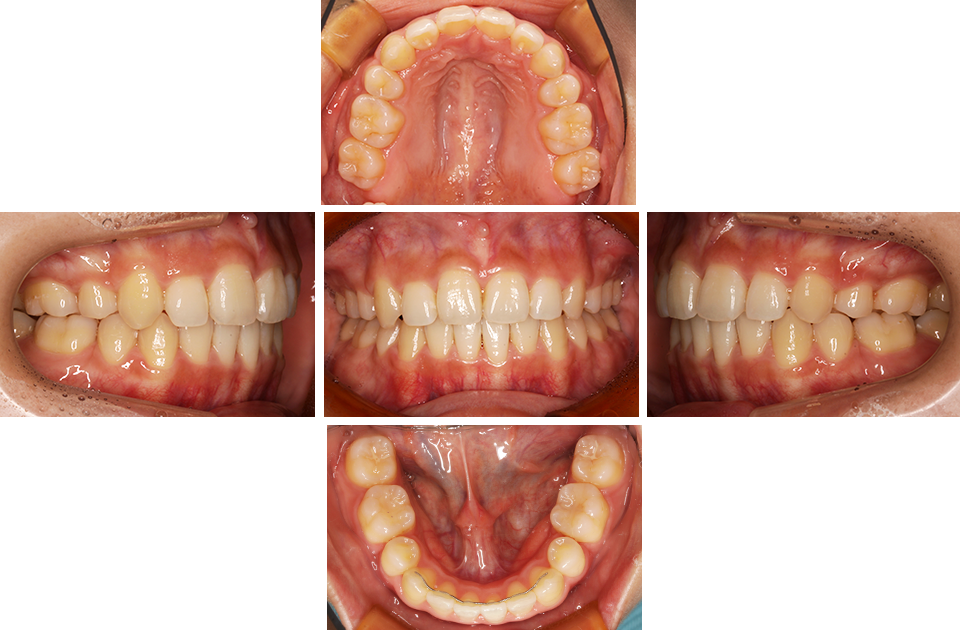

矯正前

矯正後

矯正前 正面

矯正後 正面

矯正前 右側

矯正後 右側

矯正前 左側

矯正後 左側

矯正前 上顎

矯正後 上顎

矯正前 下顎

矯正後 下顎

主訴 前歯で物が咬めない、歯並びの凸凹、出っ歯を治したい

年齢 20代

治療法 上下顎マルチブラケット装置、歯科矯正用アンカースクリュー

抜歯の有無 上顎左右側第一小臼歯、下顎左右側第二小臼歯

治療期間 1年10ヶ月